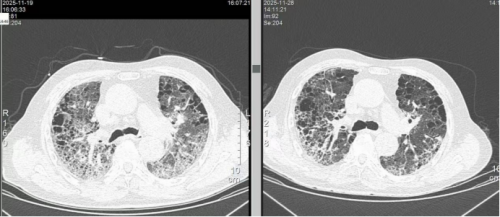

第一次入院胸部CT:

第二次入院胸部CT: